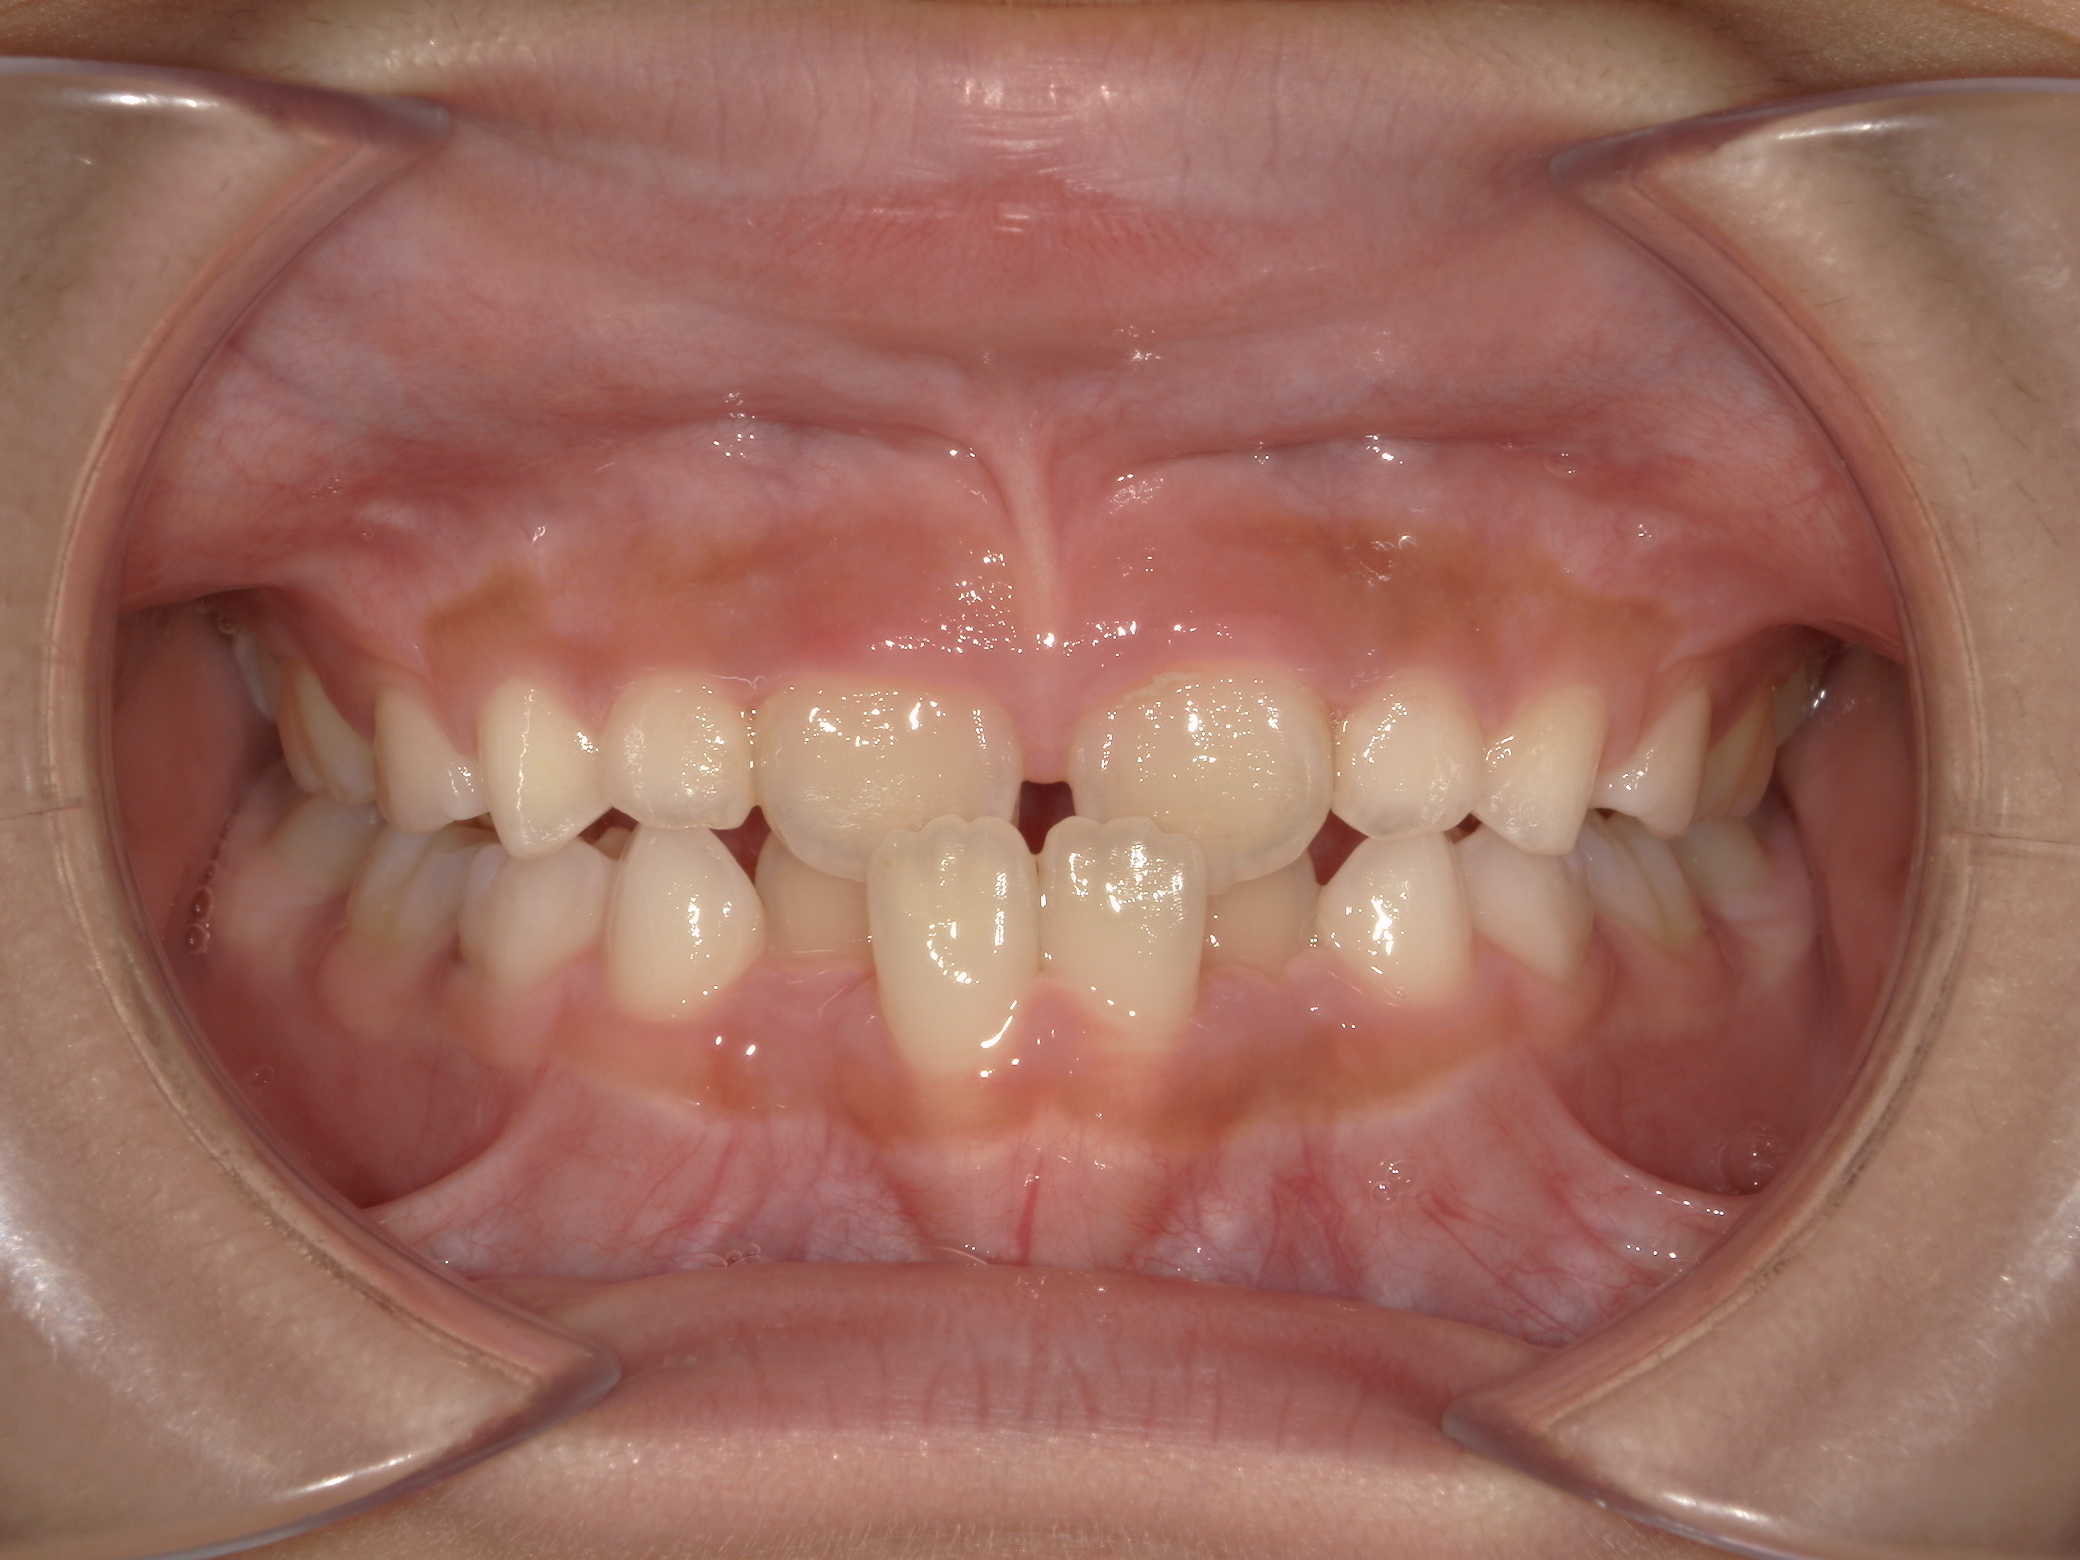

すきっ歯(11歳空隙歯列)

11歳 男性

非抜歯矯正治療

表側ワイヤー矯正

935,000円(税込)

1年2か月

隙間が歯列全体にあり、かみ合わせも深い状態でした。

上下にワイヤーを装着し、かみ合わせをあげながら隙間を閉じています。

副作用:歯根吸収・歯髄壊死・歯肉退縮・隙間の再発